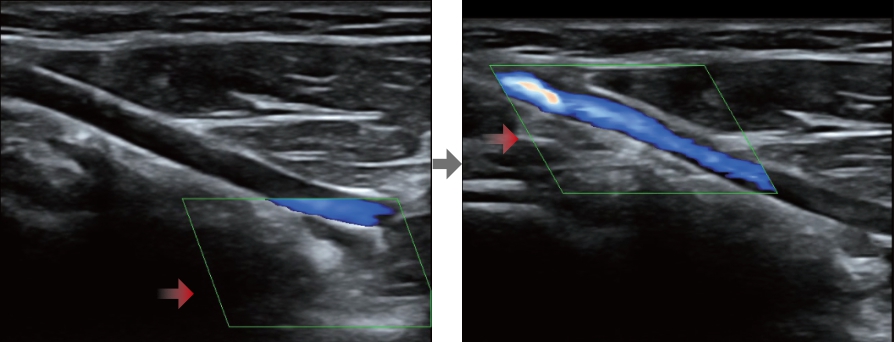

Smart Track

Con un semplice tocco, Smart Track consente di ottenere una visualizzazione ottimizzata rapida e intelligente dell'imaging vascolare. ? in grado di ottimizzare lo spettro del colore, del power e del PW mediante il funzione di tracking automatico e ridurre i passaggi che richiedono molto tempo, semplificando cosĂŹ il flusso di lavoro per gli esami vascolari.